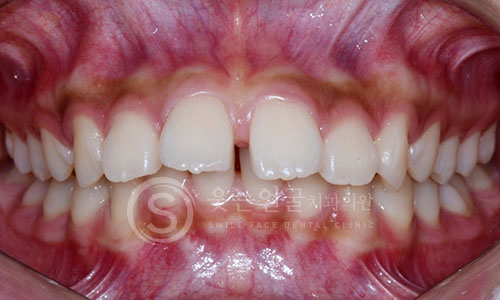

한눈에 보는

임플란트 전후사진

View more

환자 개개인의 치아 형태와 구강 구조에 맞춘 맞춤형 크라운

제작으로, 자연스러운 기능과 심미성을 동시에 제공합니다.

또한 임플란트 10년 보증 시스템으로

장기간 안심하고 사용하실 수 있습니다.